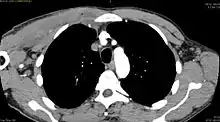

![]() أشعة مقطعية محورية على مستوى T1 توضح التهاب العضلات التقيحي الناتج عن الاصابة بالبكتيريا المكورة العنقودية الذهبية التي تستجيب للميثيسلين. ]] | |

يعتمد تشخيص التهاب العضلات التقيحي على الفحص الاكلينيكي والتاريخ المرضي للمريض. ويظل التصوير بالرنين المغناطسي هو الفحص الأكثر دقةَ لتحديد الإصابة بهذا المرض.[3]